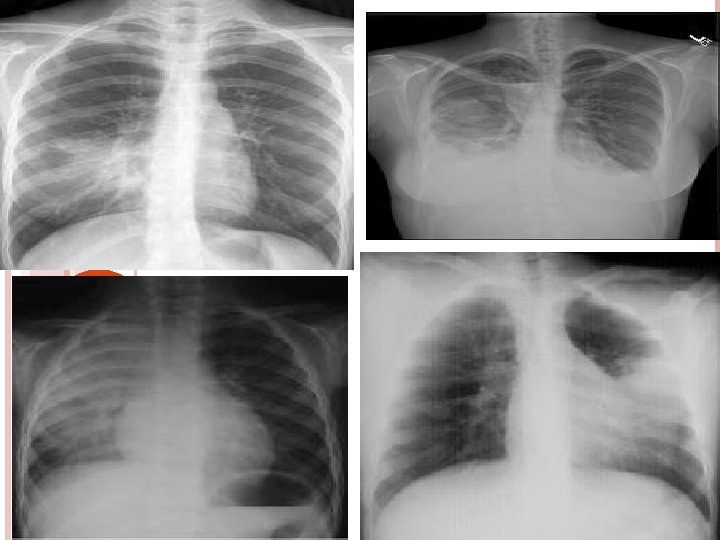

DIAGNOSTIC STUDIES History collection , physical examination Chest X-Ray lab Microbiology serology ABG

lobar Broncho pneumonia forms

HEMOPHILUS INFLUENZA Affects elderly and those with co morbid illness Mortality = 30% Associated with URTI = 2 – 6 wks before onset of illness Fever , chills , productive cough usually involves one or more lobes , sub acute bacteremia CXR = multilobar patchy bronchopneumonia / area of consolidation Cephalosporin , macrolides , quinolones

CHLAMYDIAL PNEUMONIA Single infiltrate on chest x-ray Pleural effusion , upper respiratory tract infection Tetracyclin , erythromycin Complication include acute respiratory failure

VIRAL PNEUMONIA Influenza A , B , adeno virus , RSV Parainfluenza , CMV , Corono virus Winter months , epidemics occur 2 – 3 yrs Patchy infiltrate on CXR with effusion , URTI , bronchitis , pleurisy TYPE A = AMANTIDINE , RIMANTIDINE TYPE A / B = ZANAMIVIR , OSELTAMIVIR

P. AERUGINOSA High in pre existing lung disease / cancer / homograft transplants , burns , tracheostomy , suctioning Diffuse consolidation = chest x-ray Toxic appearance , fever , productive cough , relative bradycardia , leucocytosis Amino glycosides and Antipseudomonal agents – ticarcillin , piperacillin Lung cavitations

PNEUMOCYSTITIS JIROVECI Fungal infection pulmonary diffuse bilateral alveolar pattern of infiltration. in wide spread infection lungs are massively consolidated fever , tachycardia , tachypnea , hypoxemia , non productive cough TMP – SMZ , dapsone to those intolerant to bacterim , aerosolized pentamident , primaquine , clindamycin